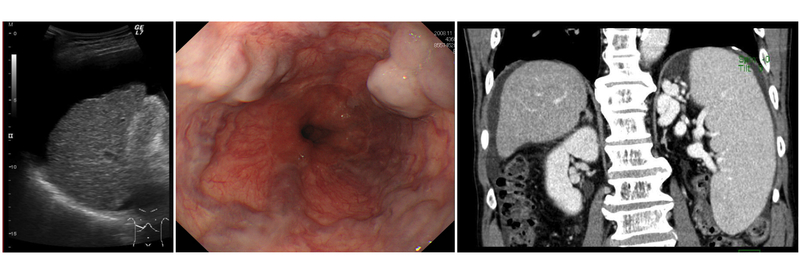

門脈圧亢進症の検査として、血液検査、超音波(エコー)検査、内視鏡検査(胃カメラ・大腸カメラ)、CT検査(X線を使って体の断面を撮影する検査)などが挙げられ、その結果を総合的に判断して治療に移行します。

慢性の肝疾患、とくに肝硬変と診断された患者さんは、ぜひ“門亢症”を念頭に置いて定期的な検査(超音波・内視鏡・CTが三種の神器)を受けてください。また、メタボリック症候群(通称、メタボ)の心当たりがある方も「隠れ肝硬変、隠れ門亢症」かもしれません。ぜひ一度、検診を受けてみることをお勧めします。